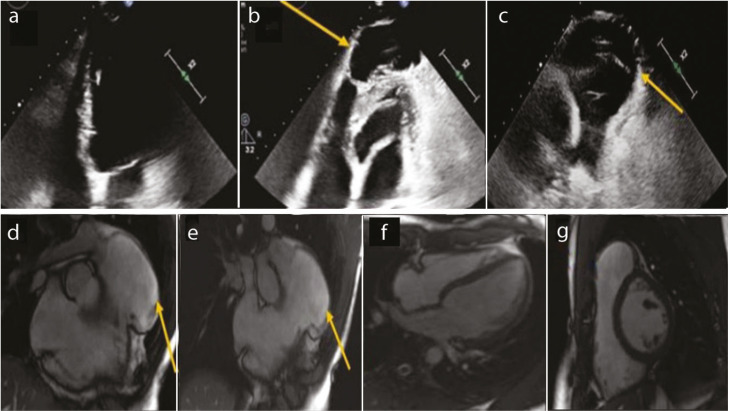

Differentiating Pectus Excavatum-Related Right Ventricul Dysfunction from ARVD: The Role of Cardiac Imaging